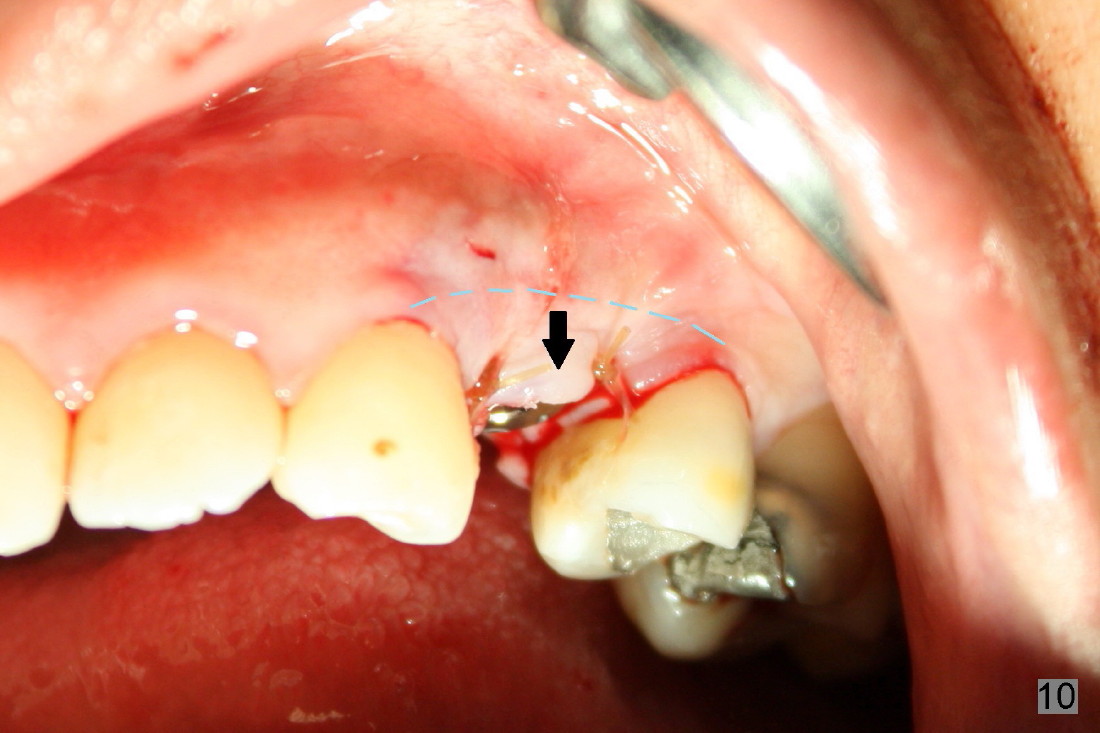

The closure of the socket involves raising and advancing both buccal and lingual flaps (Fig.10,11). When a crown is cemented, the patient is not pleased with recessive papillae (Fig.12 (arrowheads),13). It appears that flaps should be avoided to prevent cosmetic issue. Immediate implant is not enough for cosmetics; immediate provisional can close the extraction socket and support the papillae.